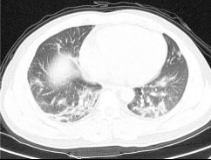

Figure 3 is showing the different stages of enhancement process of one lung image.

Figure 3. Steps of image enhancement